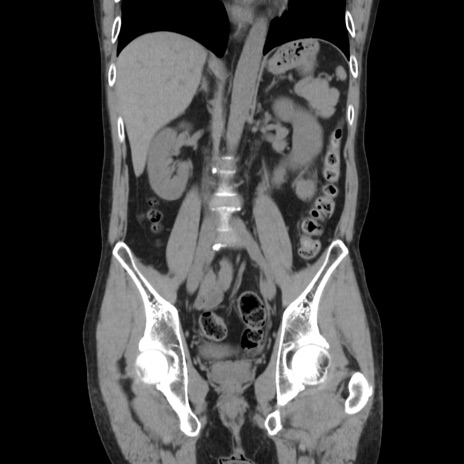

症例37(冠状断像)

【症例】40歳代 男性

【主訴】腹痛

【現病歴】4時間ほど前に電車に乗車中に臍部上より腹痛出現。徐々に増悪し起立困難となり、救急外来受診。生ものは数日食べていない。今朝お雑煮を食べた。

【身体所見】BT 36.8℃、BP 117/84mmHg、HR 91/min、SpO2 97%、苦悶様、腹部:臍上部広範囲圧痛あり、反跳痛±

【データ】WBC 8100、CRP 0.03